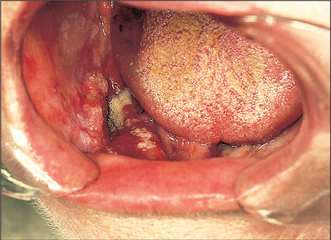

Leukoplakia (Fig. 10.1)

Fig. 10.1 Nodular leukoplakia of the lateral border of the tongue.

Clinically leukoplakia may vary from a small, circumscribed white plaque to an extensive lesion involving wide areas of the oral mucosa. The surface may be smooth or it may be wrinkled and many lesions are traversed by cracks or fissures. The colour of the lesion may be white, yellowish or grey; some are homogeneous whilst others are nodular or speckled on an erythematous base. Many lesions are soft whereas other thicker lesions feel crusty. Induration (hardening) suggests malignant change and is an indication for immediate biopsy. It is important to recognize that it is the speckled or nodular leukoplakias which are the most likely to undergo malignant change.